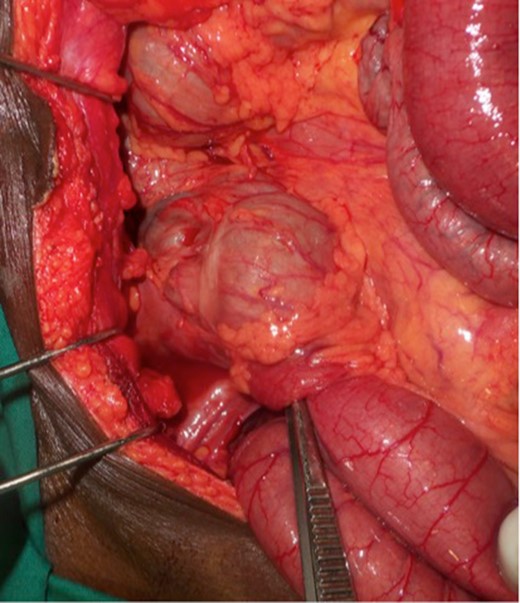

Upon laparotomy, we found an ileocecal intussusception, with mesenteric lymphadenopathies and a dilation of the whole small bowel (Fig. 3). We performed a right hemicolectomy, without attempting to reduce the intussusception, and an end-to-end ileotransverse anastomosis.